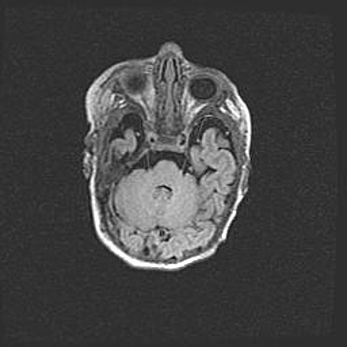

Мальформация Денди-Уокера. Киста задней черепной ямки.

Агенезия мозолистого тела.

Возраст: 2,5 месяца

Вес: 2420 г

Пол: женский

Окружность головы: 37 см

Срок гестации: 32 недели

Мальформация Денди—Уокера — редкий вид патологии ЦНС, представляющий собой врожденный порок развития каудального отдела ствола и червя мозжечка, ведущий к неполному раскрытию срединной (Мажанди) и латеральных (Лушка) апертур IV желудочка мозга. Для этогно синдрома характерна триада симптомов: гипотрофия червя мозжечка и/или полушарий мозжечка, кисты задней черепной ямки, гидроцефалия различной степени. В 70% случаев порок сочетается и с другими аномалиями головного мозга, в частности с агенезией мозолистого тела.